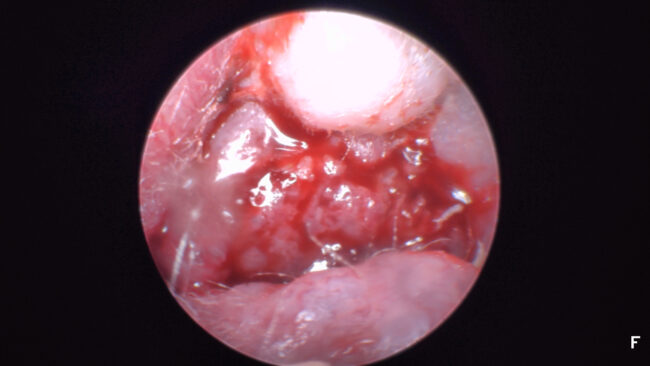

Otoendoscopie 11 : Carcinome Epidermoïde

Les carcinomes de l’oreille moyenne sont des tumeurs assez peu fréquentes mais toujours très délabrantes. L’examen otoscopique ou otoendoscopique est insuffisant pour en évaluer l’ampleur. L’imagerie en coupe est toujours nécessaire. L’occasion de rappeler que, chez le chat, une otite externe suppurée est quasi systématiquement l’expression du développement d’une néoformation (polype, tumeur) de l’oreille moyenne…